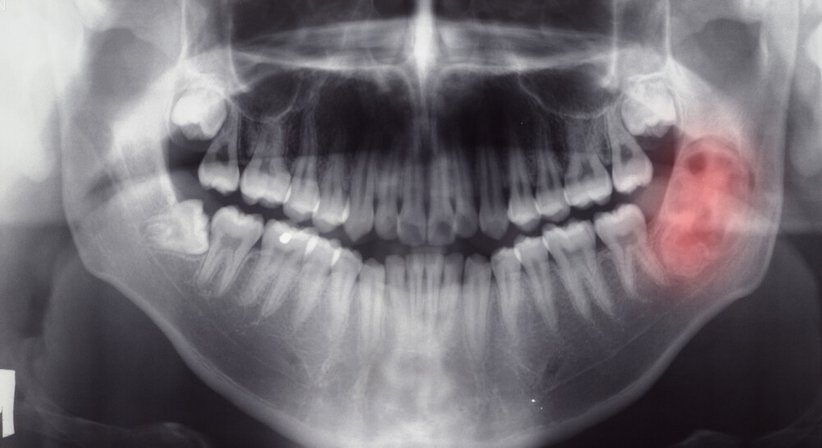

Tumorerkrankungen im Kopf- und Halsbereich sind relativ häufig, weshalb der Vorsorge eine zentrale Rolle zukommt. Frühzeitig erkannt sind die Heilungschancen in vielen Fällen sehr gut.

Die Tumorvorsorge schafft vor allem für Raucher sowie Menschen mit chronischer Heiserkeit und einem schlechten Zahnstatus Sicherheit. Bei der endoskopischen Kontrolluntersuchung werden u.a. die Schleimhäute im Nasen-, Mund-, Rachen- und Kehlkopfbereich auf Veränderungen hin beurteilt. Zudem wird die Beweglichkeit der Stimmlippen überprüft und mittels Ultraschall abgeklärt, ob Lymphknoten vergrößert sind.